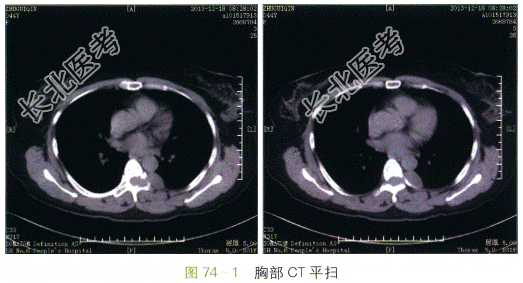

胸部CT(见图74-1~图74-2)显示后纵隔脊柱左旁哑铃型软组织密度肿块,边界清晰,边缘光滑,左侧椎间孔明显增宽扩大,肿块通过椎间孔同时累及椎管内外。平扫CT值约35Hu,增强后肿块可见均匀中度强化,CT值约49Hu。

读片分析:本例患者的病灶定位于后纵隔椎旁,病灶的形态学特点为哑铃状,通过扩大的椎间孔同时累及椎管内外,该表现为神经源性肿瘤较为特异性的征象,因此最终诊断将神经源性肿瘤放在首位。手术病理证实该例患者为神经鞘瘤。